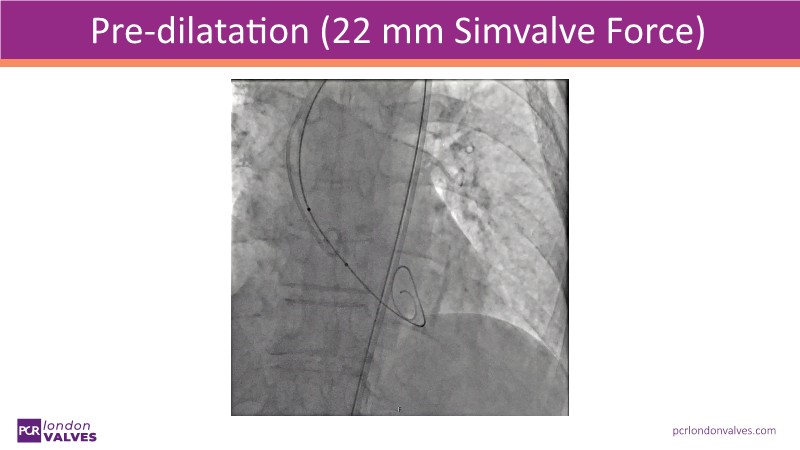

This session offers an in-depth review of complex TAVI cases, focusing on overcoming clinical challenges and achieving optimal outcomes with the Evolut FX+ device. Participants will learn about recent advances in TAVI indications for younger and asymptomatic patients, strategies for managing TAV in surgical aortic valve (SAV) patients including redo TAVI, and explore technological innovations designed to address complex anatomical scenarios.